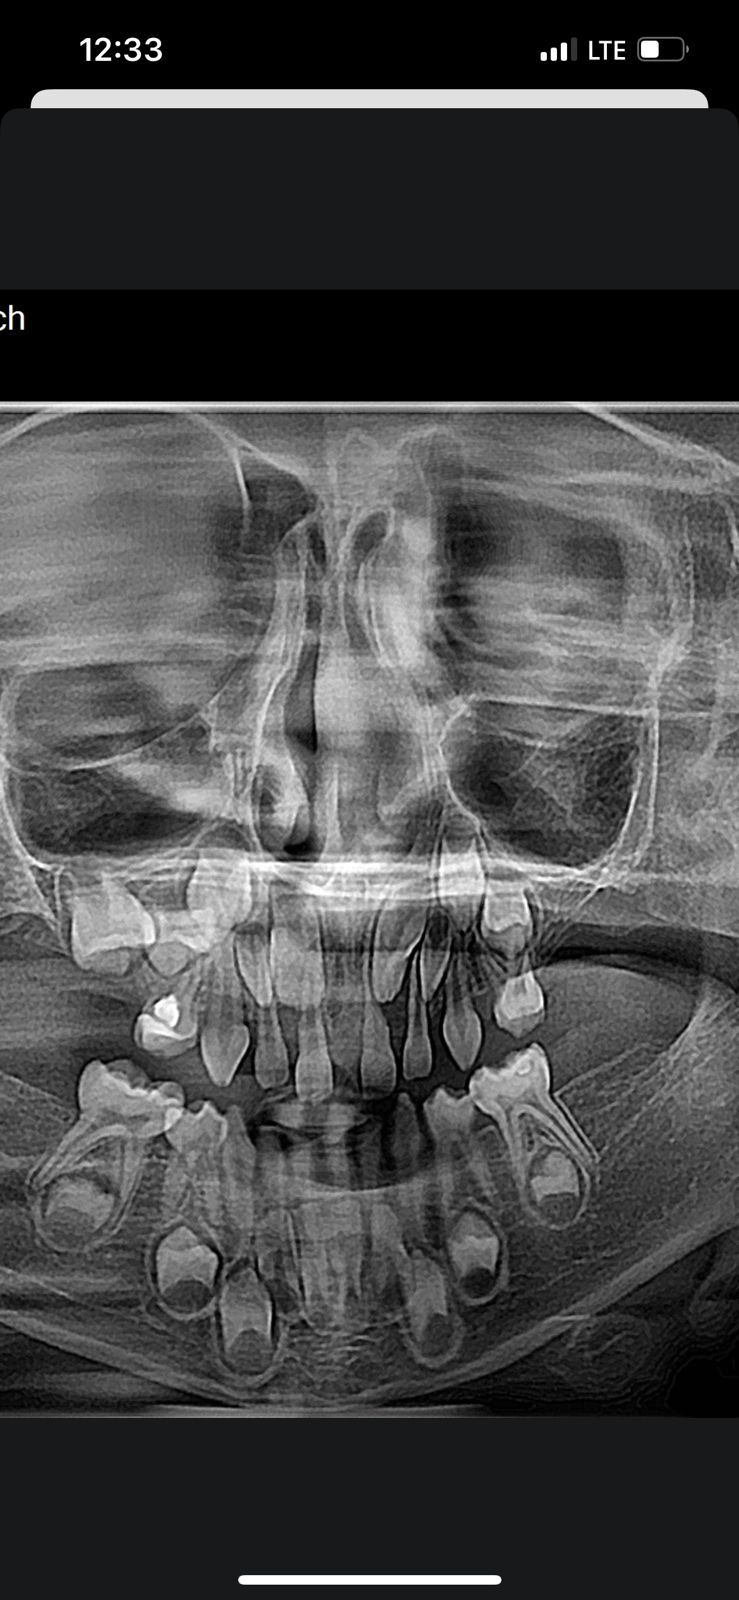

Здравствуйте, моему сыну 5 лет и я заметила, что у него не вылезли все 20 молочных зубов (как должно быть в его возрасте), а всего 17. Забила тревогу, сделала снимок:

Уже получив снимок я поняла, что что-то тут не так, зубов меньше, чем должно быть. Хорошо, что на данный момент были в отпуске и нашли врача, которая сказала, что у него не будет 9 постоянных зубов (9!!!!) - одной пятерки, двух шестерок и двух семерок.